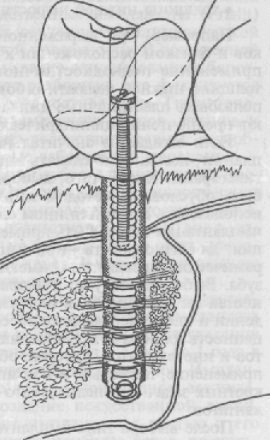

Egy tipikus mechanikusan aktív implantátum kialakítás javasolt M.Z.Mirgazizovym, V.E.Ponterom, V.I.Itinym, úgynevezett CIC (ábra. 284). Ez az implantátum tartalmaz a struktúrájában egy mechanikusan aktív elemeinek ötvözetek „memória” alak formájában vékony szálak szimuláló periodontális ínszalag. Építmény figyelembe véve a szerepe a mechanikai tényezők a modellezési folyamatok reparatív remodelling és csontszövet helyreállítására, amely a következő:

• Biztosítani kell a képességét, csont generálni elektromos potenciál hatása alatt mechanikai behatásoktól.

• Támogatás kvázi-állandó elektromos aktivitását csont miatt a belső mechanikai igénybevételnek csontszövet.

• Szabályozási hatása nyomóerő szaporodását és az extracelluláris mátrix komponensek a csontszövet.

• stimulálása funkcionális aktivitásának a csontszövet.

• Növelje a csont szint beállítás zónákban megnövekedett terhelés, a mennyiség, mint egy átalakítás ciklusok és erősítésével javító eljárásokat válaszul előfordulása mikro túlterhelés miatt.

• aktiválása felszívódást folyamatok területén az a terhelés csökkentése növeli a frekvencia átalakítás ciklus.

Ábra. 284. A hengeres implantátum alakmemória.